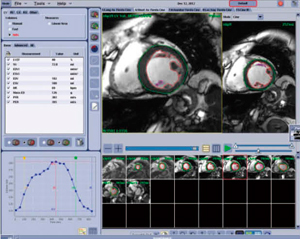

2.Cardiac VX

“Cardiac VX”は,6つのモードを持つ心臓MRIの解析・レポーティング用アプリケーションである。新しいGuided User Interfaceを搭載し,従来の解析ソフトウェアと比較して,より直感的で簡便な操作性を実現している。6つのモードでは,それぞれ心機能解析,血流解析,パーフュージョン解析,LGE解析,PFO(卵円孔開存症)解析,T2*マップ解析が可能であり,ソフトウェアが起動された時点で解析に必要なデータだけが自動的に選択される。

心機能解析においては,左室および右室の解析が可能であり,わずか数クリックで心筋内膜と外膜がトレースされるようになった。従来ソフトウェアと比較して,トレース精度が大幅に向上し,乳頭筋の除去もボタン1つで切り替えられるため,よりスムーズな解析が可能となっている(図6)。

図6 Cardiac VX(左室解析の画面)